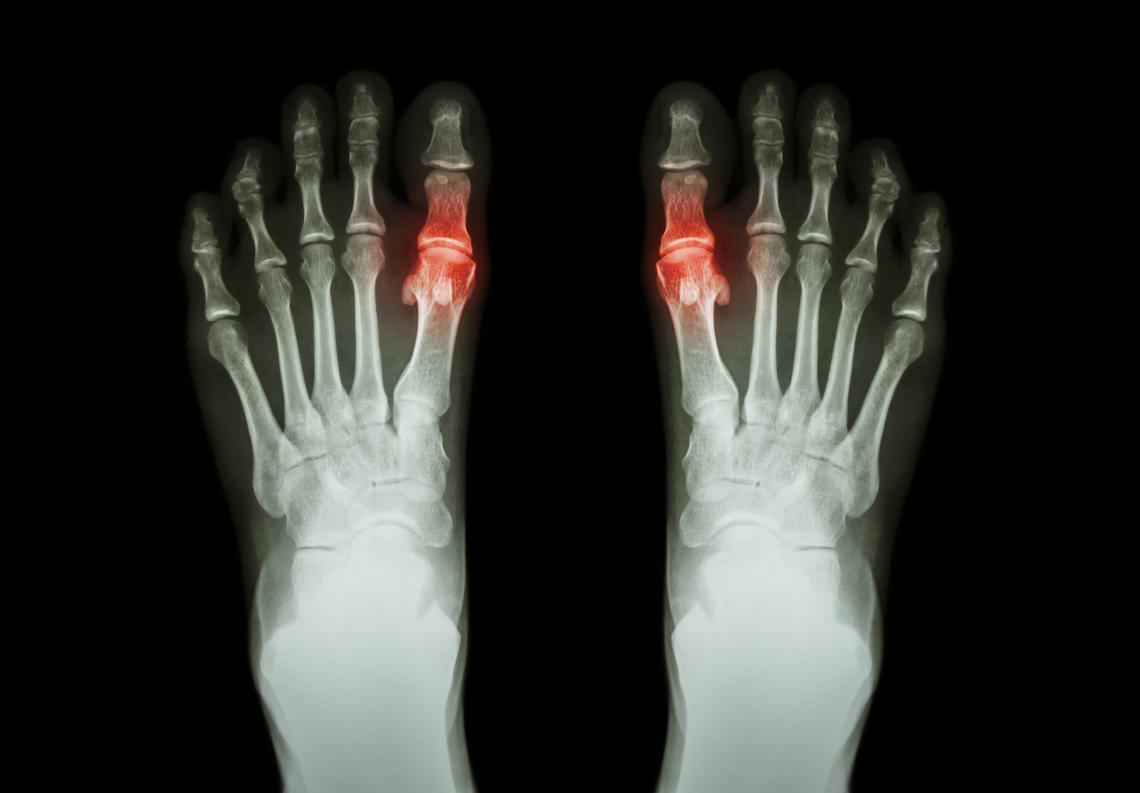

Bone and joint diseases are the primary cause of disability in Canada, with osteoarthritis affecting one in nine Albertans. This number is expected to double by 2031. In any given year, a Canadian living with a bone and joint disease is two to three times more likely to be hospitalized, require physiotherapy, and multiple primary care or specialist visits than someone without a chronic condition. Currently, there are no cures for the three most common musculoskeletal (MSK) diseases: osteoarthritis, inflammatory (rheumatoid) arthritis, and osteoporosis.